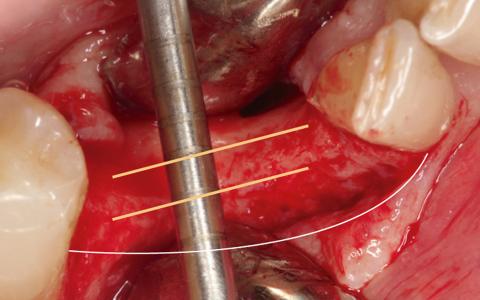

Paciente de 55 años al que le realizaron la extracción de los dientes 4.2- 4.2 con quistes apicales y bolsas superiores a 9 mm, con abscesos recurrentes. En la exploración clínica se observó una pérdida de tejido queratinizado y un defecto transversal. Se decide hacer un IGL para tener un buen tejido y así poder proteger el injerto.

Plan de tratamiento: Expansión y regeneración diferida.